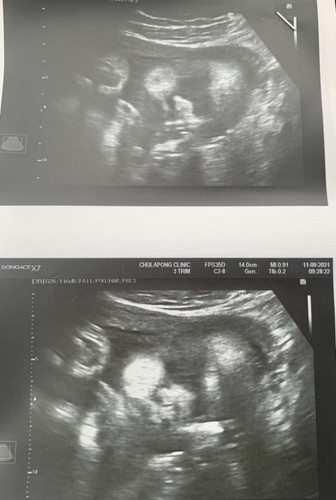

33 week แล้ว ได้ลูกสาว ทีมตุลาคม มีแม่คนไหนยังคิดชื่อเล่นลูกไม่ออกสักที แม่ๆช่วยตั้งชื่อเล่นน่ารกๆให้หน่อย😁😊